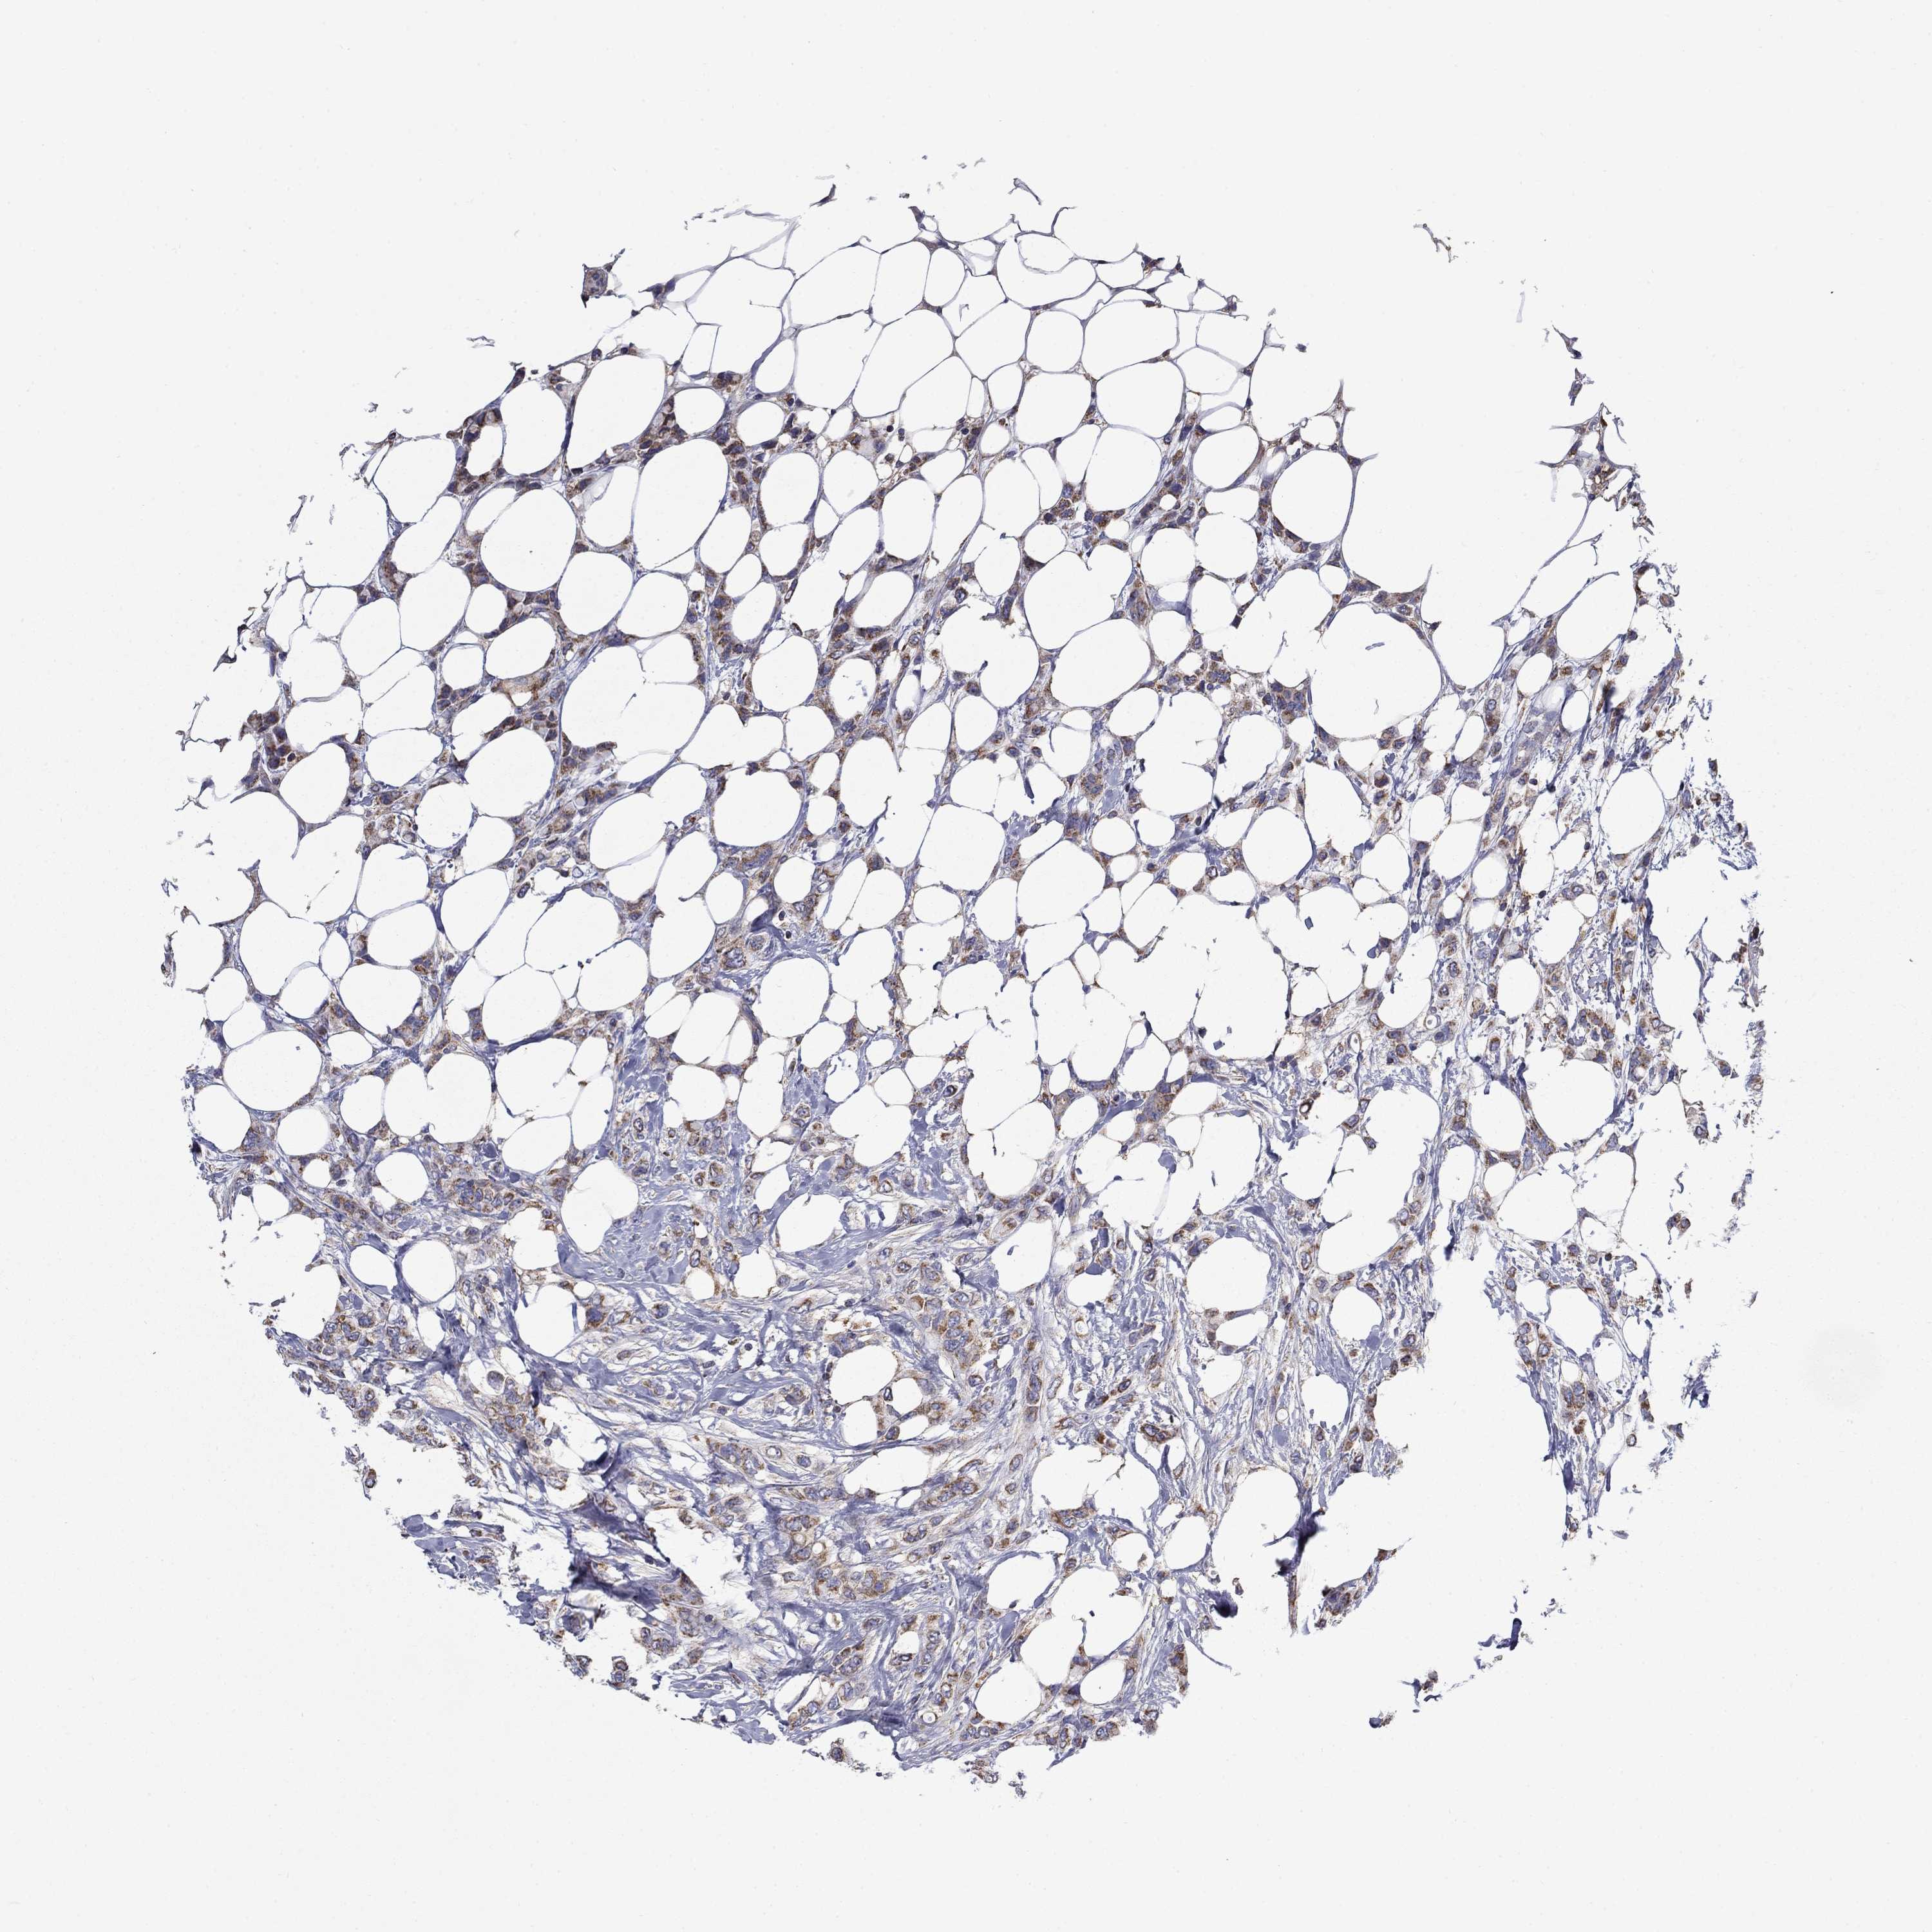

BRCA TCGA BRCA VALIDATION PROTEIN EXPRESSION

Breast cancer

Human cancer